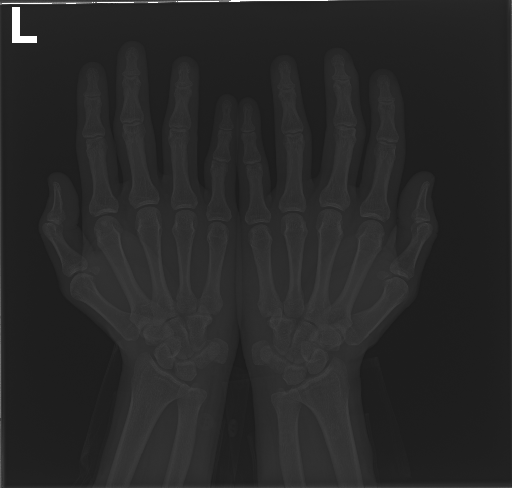

In this work, we focus on a subset of the MURA dataset [17] containing only hand images. In total, we have 5,543 images of 2,018 studies of 1,945 patients. Each study is labeled as negative or positive, where positive means that there was an anomaly diagnosed in this study. There are 521 positive studies, with a total of 1,484 images. Figure 1 shows some examples from the dataset. In summary, our contributions are as follows:

Hand Localization

To further improve the detection of hands, and in particular split the images where two hands are depicted on one image, we manually labeled approximately 150 bounding boxes in the images. Using this small dataset, we fine-tune a pre-trained single shot multibox detector (SSD) [12] with MobileNet as taken from TensorFlow. An exemplary results can be seen in Figure 3.